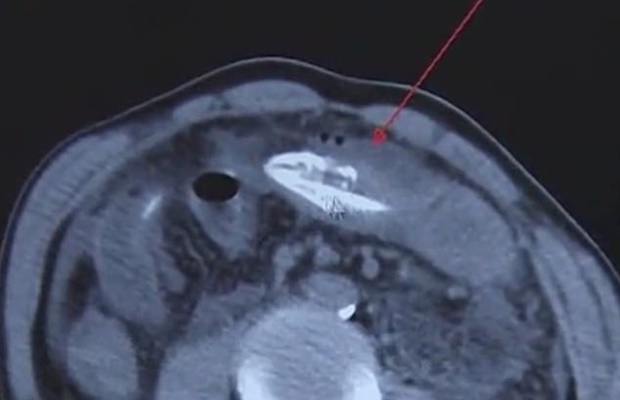

20일 복통을 호소하며 병원으로 실려 온 환자를 본 의료진은 적잖은 충격을 받았다. 배 속에 살아있는 장어 한 마리가 꿈틀거리고 있었기 때문이다. 보도에 따르면 평소 극심한 만성변비에 시달리던 환자는 장어가 변비에 도움이 된다는 민간요법을 듣고 20㎝ 길이 장어를 산 채로 항문에 집어넣었다. 삽입 직후 배가 찢어지는 듯한 고통에 시달렸지만 “부끄러워서 진료를 못 받겠다”고 버티다 결국 병원으로 향했다.

수술 당시 장어는 이미 죽어 있었으나, 환자는 세균 감염이 심각한 상태였다. 위장 등 복부에는 오염물질이 가득 차 있었으며, 대장에는 장어가 움직이고 깨물면서 생긴 구멍도 나 있었다. 그래도 다행히 수술 후 경과가 좋아 장어를 제거한 지 3일 만에 환자는 퇴원했다.